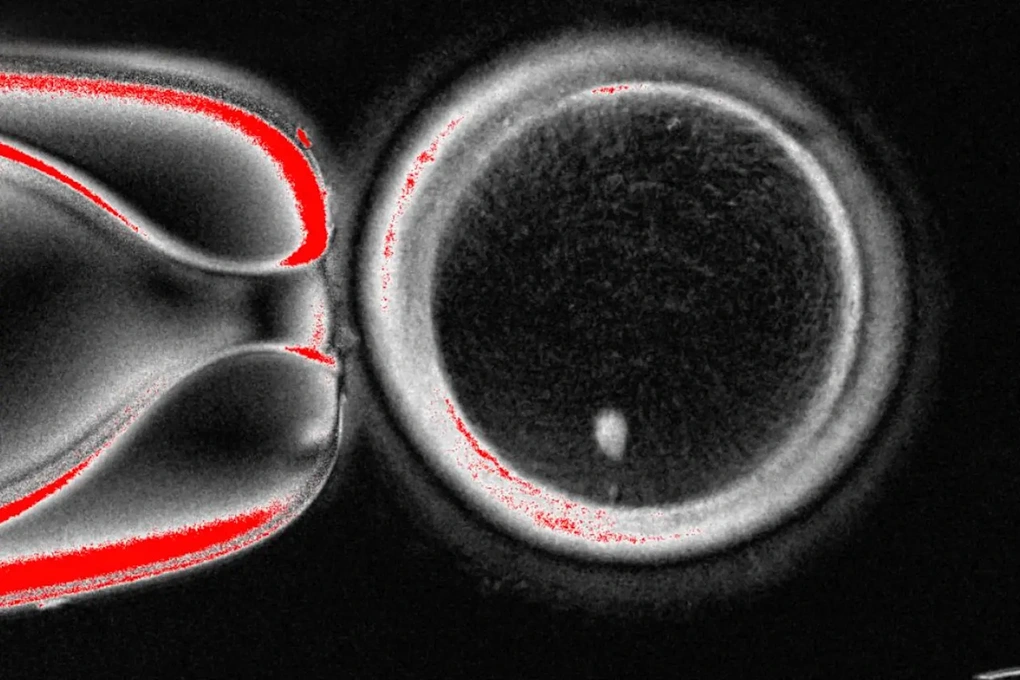

Hình ảnh không ghi ngày tháng này do Phòng thí nghiệm Mitalipov, Trường Đại học Khoa học và Sức khỏe Oregon, Mỹ, cung cấp, cho thấy hình ảnh dưới kính hiển vi của một quả trứng người có chứa nhân lấy từ tế bào da (ảnh: AP).

Nghiên cứu được công bố trên tạp chí Nature Communications đã trình bày chi tiết cách các nhà khoa học Mỹ tạo ra một tế bào trứng người, còn gọi là noãn bào, bằng cách cô lập nhân của một tế bào da và cấy ghép nó vào trứng của người hiến tặng vốn không có nhân.

Sau khi cấy ghép nhân tế bào da vào trứng được hiến tặng, tế bào trứng vẫn không thể sống được vì nó chứa đầy đủ 46 nhiễm sắc thể, thay vì 23, số lượng chính xác của trứng người.

Sau đó, các nhà khoa học đã áp dụng một xung điện nhẹ và xử lý hóa học để loại bỏ một nửa số nhiễm sắc thể khỏi trứng đó và để lại số lượng nhiễm sắc thể phù hợp cho quá trình sinh sản.